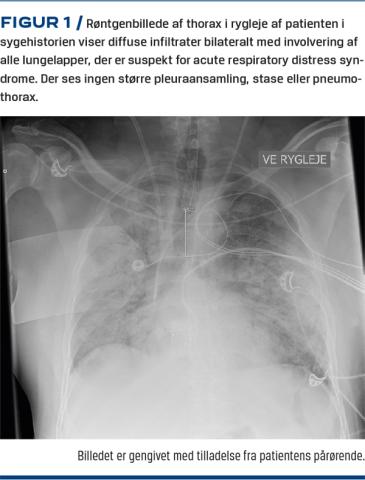

En 50-årig mand blev indbragt til et hospital genoplivet efter flere præhospitale hjertestop. Han havde ingen tidligere kendte sygdomme, var erhvervsaktiv, fysisk aktiv, aldrig-ryger og i øvrigt uden kendte risikofaktorer for iskæmisk hjertesygdom. Han havde været syg med feber og hoste i en uges tid op til hjertestoppene. Symptomerne var taget til i de sidste par dage med en samtidig følelse af åndenød. Der var ingen klager over brystsmerter. Han havde konsulteret læger over telefon flere gange i forløbet, og fik dagen inden hjertestoppene udskrevet antibiotika på mistanke om pneumoni. Om aftenen inden indlæggelsen havde han tiltagende åndenød med respirationsbesvær og manglende hostekraft. Pga. yderligere forværring i løbet af natten, ringede hans hustru 112, og i forbindelse med opkaldet mistede han bevidstheden. Der blev konstateret hjertestop, og hustruen påbegyndte hjerte-lunge-redning (HLR). Ambulancen ankom ca. 10 minutter senere. Den første registreret hjerterytme på skadestedet var asystoli. Efter HLR og indgift af adrenalin konverterede patienten til pulsløs elektrisk aktivitet (PEA) og blev intuberet. Han opnåede genoprettelse af spontan cirkulation (ROSC) ca. 12 minutter efter ambulancens ankomst. Efter ROSC havde han fortsat respiratorisk svigt med svær hypoksi. Han var i øvrigt svært cirkulatorisk labil og fik efterfølgende kortvarigt hjertestop to gange på vej til hospitalet. Ved ankomsten var han fortsat svært cirkulatorisk labil og fik hjertestop yderligere fem gange i akutmodtagelsen. Under hjertestoppene var hjerterytmen hver gang PEA med 2-6 minutter til hver episode af ROSC. Han havde på intet tidspunkt i forløbet stødbar hjerterytme. Efter noget tid blev han stabiliseret på store doser adrenalin og kørt på intensivafdelingen, hvor der blev givet maksimal organunderstøttende behandling inklusive infusion af store doser noradrenalin og specielt adrenalin. Han blev respiratorbehandlet i henhold til acuterespiratorydistresssyndrome (ARDS)-guidelines [4], og samtidig blev der påbegyndt dialysebehandling pga. svær metabolisk acidose. Han havde nedsat bevidsthedsniveau med Glasgow comascale 3 i hele forløbet. Der var ingen klinisk mistanke om en intrakraniel katastrofe. Han afventede overflytning til Rigshospitalet med henblik på veno-arteriel ekstrakorporealmembraneoxygenering (VA-ECMO), men gik desværre ad mortem syv en halv time efter ankomsten til hospitalet trods maksimal organunderstøttende behandling. Han blev senere konstateret positiv for SARS-CoV-2.De øvrige parakliniske undersøgelsesresultater er vist i Tabel 1 og Figur 1.

In this case report, a 50-year-old man who had no medical history, presented with multiple cardiac arrests following a week with progressing symptoms of pneumonia. After achieving return of spontaneous circulation he presented with respiratory failure with severe hypoxia, septic shock, and multiple organ failure. A chest X-ray showed signs of acute respiratory distress syndrome. Despite aggressive intensive care management, the patient died 7.5 hours after admission. Severe acute respiratory syndrome coronavirus 2 (SARS-CoV-2) was later confirmed, and the presumed cause of death was SARS-CoV-2 pneumonia. In conclusion: coronavirus disease 2019 (COVID-19) can lead to a fatal outcome in younger healthy residents, who are not treated timely in case of severe symptoms like dyspnoea.